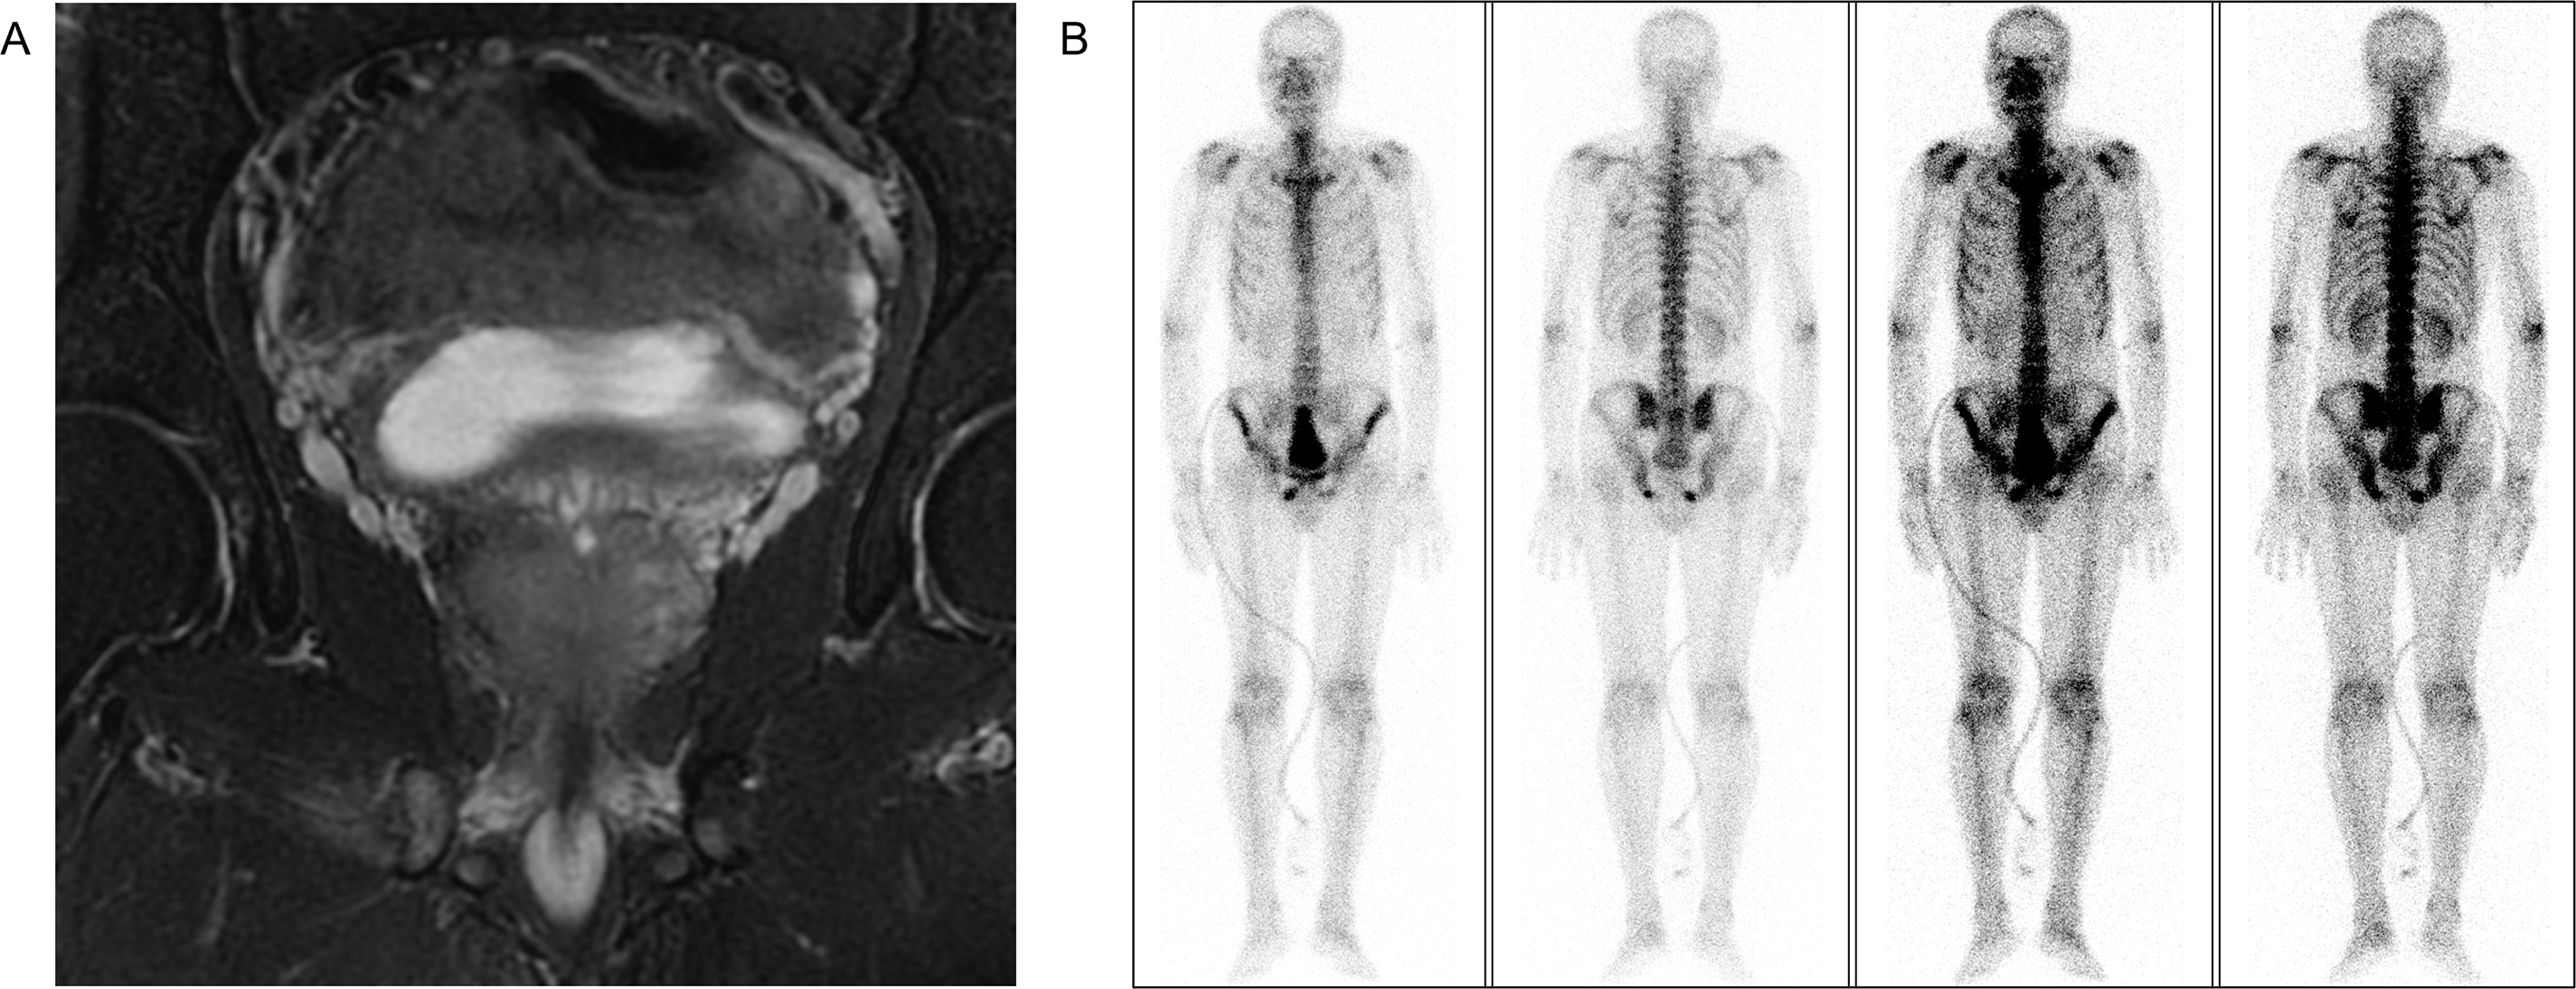

A 51-year-old man was admitted to the First Affiliated Hospital of Anhui Medical University in April 2020 with a six-month history of intermittent dysuria, accompanied by urinary frequency, urgency, and pain. The serum PSA level of the patient was 5.810 ng/mL at the outpatient visit, and urodynamic testing confirmed an overactive bladder. The prostate nuclear magnetic resonance imaging (MRI) revealed a prostate size of approximately 35.0 mm × 36.2 mm × 45.6 mm (Fig. 2A). A long T1 and short T2 signal was observed in the right peripheral and central zones, accompanied by a high diffusion-weighted imaging (DWI) signal and a significantly reduced apparent diffusion coefficient value. The bladder was moderately filled with a normal wall thickness. No significantly enlarged lymph nodes were detected in the pelvic or bilateral inguinal regions, and fluid accumulation was not observed in the pelvic cavity. Bone scintigraphy revealed increased metabolic activity in the bilateral ischial pelvis (Fig. 2B). Subsequently, a 12-core ultrasound-guided prostate biopsy was performed, and the pathological results confirmed that all 12 cores were prostate acinar cell carcinomas, while perineural invasion was observed in five cores. Gleason scores were as follows: One core 5 + 5 = 10, six cores 4 + 5 = 9, four cores 5 + 4 = 9, and one core 4 + 4 = 8 (Fig. 3A). After thorough discussions with the patient and family, a robot-assisted laparoscopic radical prostatectomy with pelvic lymph node dissection was scheduled. Intraoperatively, the prostate was firmly adherent to the rectal and right pelvic wall, rendering complete resection unfeasible. Consequently, a prostate debulking surgery was performed, with partial prostate tissue, bilateral vas deferens, and seminal vesicles resection, and bilateral pelvic lymphatic adipose tissue removal. Postoperative pathology report confirmed this case as prostatic adenocarcinoma, with an overall Gleason score of 4 + 5 = 9 (Fig. 3B). Cancerous tissue was observed in the right and left lobes and the prostatic apex. The tumor burden was approximately 90%. Perineural invasion was present (+). Tumor emboli presence in interstitial blood vessels cannot be excluded. No definitive tumor involvement was observed at the specimen margins. No cancerous tissue was detected in the seminal vesicles, and no definite metastasis was observed in the right and left pelvic lymph nodes. The patient was successfully discharged after surgery and subsequently received androgen deprivation therapy with bicalutamide. The patient also received 95% PTV1: 7000c Gy/35f/48d, 95% PIV2: 5000c Gw25f/36d, for a total of 35 pelvic radiotherapy sessions from May 25 to July 20. No abnormal PSA elevation was observed during the 3.5-year follow-up.

Figure 2: Preoperative imaging evaluation. (A) Prostate MRI. (B) Bone scintigraphy